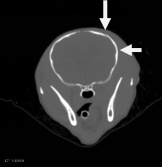

| 右侧眼眶壁内前侧骨折 |

| 右侧顶骨及颞骨骨折 |

| 大脑右侧顶部脑挫裂伤 |

| 先天性脑囟门未闭合;右侧耳道少许积液 |

1、右侧眼眶壁骨折

2、右侧顶骨及颞骨骨折伴周围软组织稍肿胀

3、大脑右侧顶部脑挫裂伤

4、先天性脑囟门未闭合

5、右侧耳道少许积液

余未见明显异常,请结合临床。